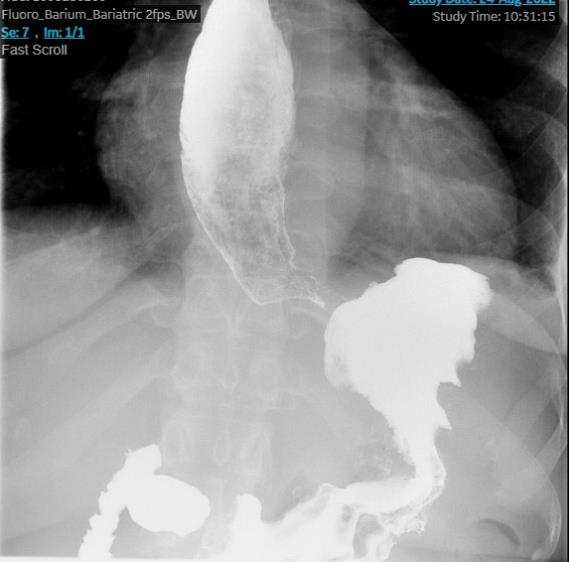

BURKITT LYMPHOMA INDUCED PSEUDOACHALASIA WITH DRAMATIC SYMPTOMATIC IMPROVEMENT POST-CHEMOTHERAPY

68

Marni H. Wilkoff1 , Emily S. Seltzer1 , Allison E. Wang1,2 , Bruno Almeida Costa1 , Bruce Gelman1

1Mount Sinai Morningside-West Hospitals, Icahn School of Medicine at Mount Sinai, New York, NY, United States;

2Mount Sinai Beth Israel Hospital, Icahn School of Medicine at Mount Sinai, New York, NY, United States 69